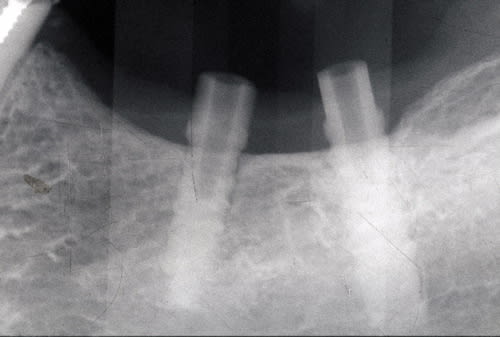

pour le débat, voici ce que j'ai posé en 1990, 1 TBR vissé + 2 zircones vissés de Sandhaus, et voici le résultat 17 ans plus tard. comme le mélange des genres va interpeller, j'explique. il s'agit là de la 2ème pose d'implant de ma carrière débutante, alors que je faisais le DU de la Salpétrière. c'était à l'époque où l'on débatait sur le risque de solidariser un implant à une dent. j'ai finalement préféré ne pas solidariser mes 2 implants 36-37 à la 34 et j'ai donc rajouté un implant en 35 par la suite; entre temps, j'avais abandonné les implants en zircone car la technique chirurgicale proposée avec ne me plaisait pas et que celle proposée pour les implants en titane me convenait davantage. il s'agissait déjà pour Sandhaus de poser les implants sans faire de lambeau et pour le débutant que j'étais, je trouvais ça trop délicat; j'ai donc terminé le cas avec un TBR en technique Branemark plus sécurisante.